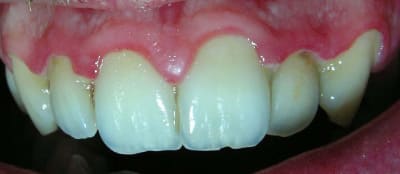

...Et les photos prises aujourd'hui, juste avant la séance de démonstration du contrôle de plaque.

Je n'ai pas fait de microscope durant cette séance car on sort tout juste du traitement antibiotique et ça n'aurait certainement pas montré grand chose.

Le but est de le revoir dans un mois pour déterminer sa motivation et son efficacité en matière de contrôle de plaque. Et pour voir comment la flore recolonise le terrain avant de lithotritier.